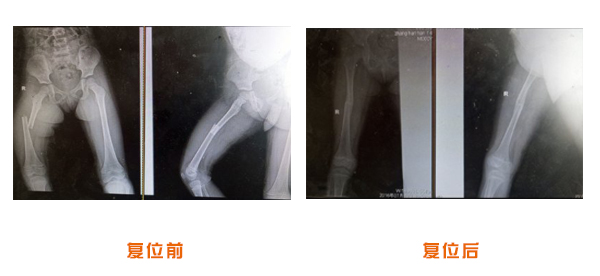

復位前后對比

尺橈骨骨折治療前后